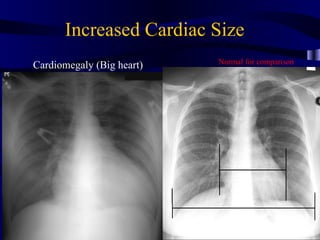

Heart Size • Normal is <50% on PA upright radiograph

Increased Cardiac Size Normal for comparison Cardiomegaly (Big heart)